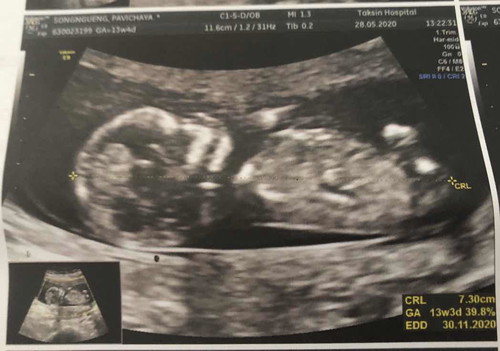

เพศลูก

13w4d น่าจะได้ลูกชาย เห็นจู๋ค่อนข้างชัด หมอบอก555 อิแม่ตื่นเต้น